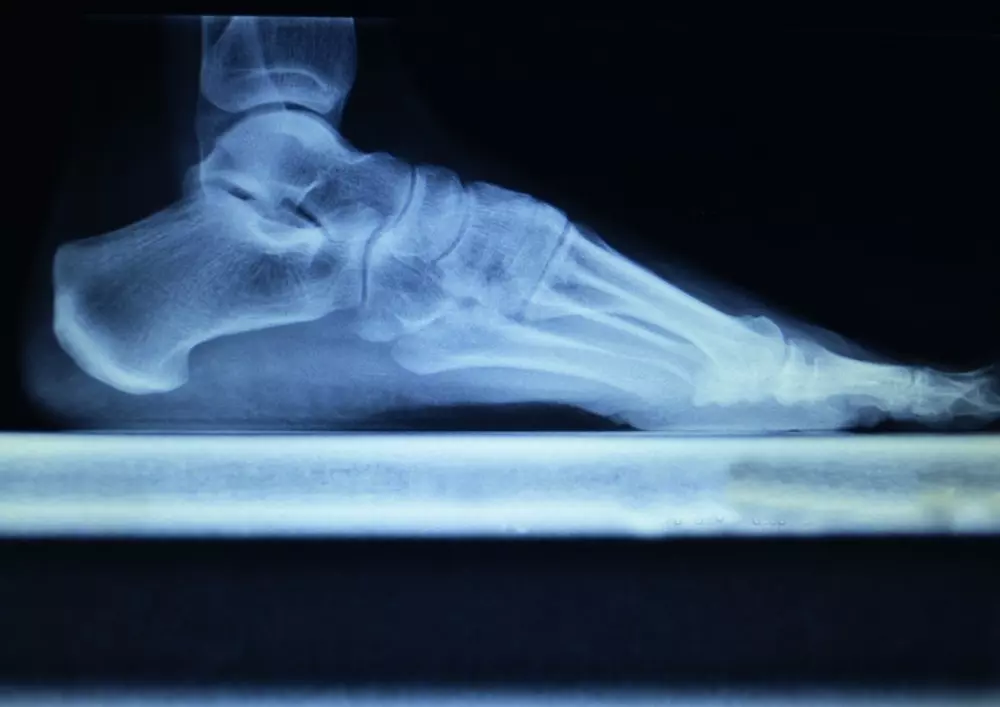

- indywidualnych wkładkach ortopedycznych,